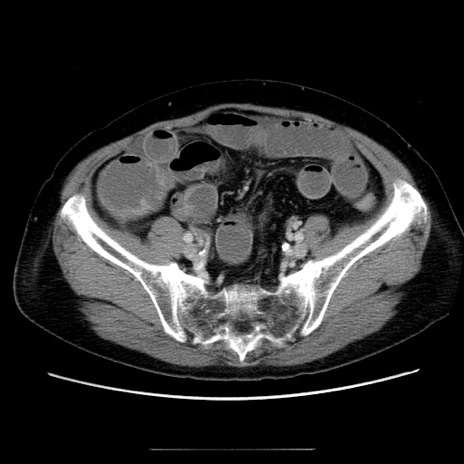

症例5(横断像)

冠状断像

【症例】70歳代女性

【主訴】お腹が張る

【現病歴】1週間くらい前から腹部膨満の自覚あり。昨日夜から増悪したため、本日救急外来受診。

【身体所見】意識清明、BT 36.5℃、BP 165/106mmHg、HR 80bpm、SpO2 98%、腹部:膨満、軟、自発痛・圧痛なし、触診にて不快感あり、腸蠕動音:減弱

【データ】WBC 12600、CRP 1.04